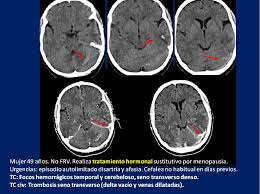

Cerebral venous thrombosis is characterized by infarction with focal neurologic deficits and increased intracranial pressure. Cerebral venous thrombosis (cvt) refers to occlusion of venous channels in the cranial cavity, including dural venous thrombosis, cortical vein thrombosis and deep cerebral vein thrombosis. This prevents blood from draining out of the brain. It's most common clinical manifestations are headache, seizures, altered consciousness, and neurological focal signs on. Cerebral venous thrombosis is diagnosed on imaging. Cerebral venous thrombosis (cvt) is an uncommon but serious disorder. Cerebral thrombosis is arterial thrombosis in one of the cerebral arteries; There may be clues on a noncontrast ct of the head, such as the dense triangle sign or the cord sign, but the ct will be normal in at least 30% of cases and many of the abnormal findings are nonspecific. 1, 2 significant equipoise exists around multiple treatment. The rarity of the disease has made it difficult to study in clinical trials, and current treatment guidelines for cvt are consensus based. Cerebral venous thrombosis (cvt) is a blood clot of a cerebral vein in the brain. Esta enfermedad sucede cuando una de las arterias que suministra sangre al cerebro se estrecha, por lo general a causa de asterosclerosis, y el aporte sanguíneo al cerebro resulta tan precario que la sangre forma una coágulo en la porción. This chain of events is part of a stroke that can occur in adults and children.

There may be clues on a noncontrast ct of the head, such as the dense triangle sign or the cord sign, but the ct will be normal in at least 30% of cases and many of the abnormal findings are nonspecific. Deep cerebral vein thrombosis is a subset of cerebral venous thrombosis involving the internal cerebral veins, often coexisting with cortical vein thrombosis or dural venous sinus thrombosis, and with different clinical presentations relying on which segment is involved. Many factors, alone or combined, can cause cvt. Cerebral venous thrombosis (cvt) refers to occlusion of venous channels in the cranial cavity, including dural venous thrombosis, cortical vein thrombosis and deep cerebral vein thrombosis. Cerebral venous sinus thrombosis (cvst) occurs when a blood clot forms in the brain's venous sinuses. Although cvt can occur at any age, it most commonly affects neonates and young adults. Symptoms may include headache, abnormal vision, any of the symptoms of stroke such as weakness of the face and limbs on one side of the body and seizures. Cerebral venous thrombosis is characterized by infarction with focal neurologic deficits and increased intracranial pressure.